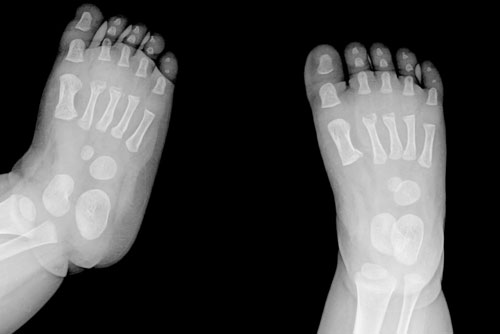

5-  Geblikte Cücelik - Çarpık Ayak -  Eksik veya Fazla Parmak

Anne karnında tespit edilebilecek anormallikler arasında bebeğin parmaklarındaki yapışıklık, parmak sayısının fazla ya da eksik olması ile bebeğin uzuvlarının fazla uzun veya kısa olması gibi sorunlar tespit edilebiliyor. Bu sorunlar yapılacak küçük operasyonlarla ve her gün gelişen protezlerle düzeltilebiliyor. Uzmanlar tarafından bebekte oluşabilecek; çarpık ayak, kalça çıkıklığı, gebelikte cücelik belirtileri, boyun eğriliği gibi ciddi uzuv ve omurga gelişim bozuklukları, diğer uzuv bozukluklarına göre çok daha önemli iskelet anomalilerinden bazıları olarak belirtiliyor.